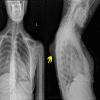

Osteochondromas commonly affect the proximal humerus, pelvis, and knee but are rarely seen on flat bones. Herein, we present the case of a 15-year-old female patient with osteochondroma located at the dorsal aspect of the scapula. The patient was admitted to the Orthopedics and Traumatology Department with the complaint of a mass on the left upper back for five years. The patient complained of the inability to sleep in the supine position, pain with shoulder motion, and cosmetic discomfort for two years. X-rays of the left shoulder revealed a bony mass arising from the dorsal aspect of the left scapula. The patient underwent an operation, and a specimen was sent for histopathologic examination. The histopathologic investigation confirmed the diagnosis of non-malignant transformation osteochondroma. While osteochondroma is not common in the scapula, it should be kept in mind that the most common benign tumor of the scapula is osteochondroma.